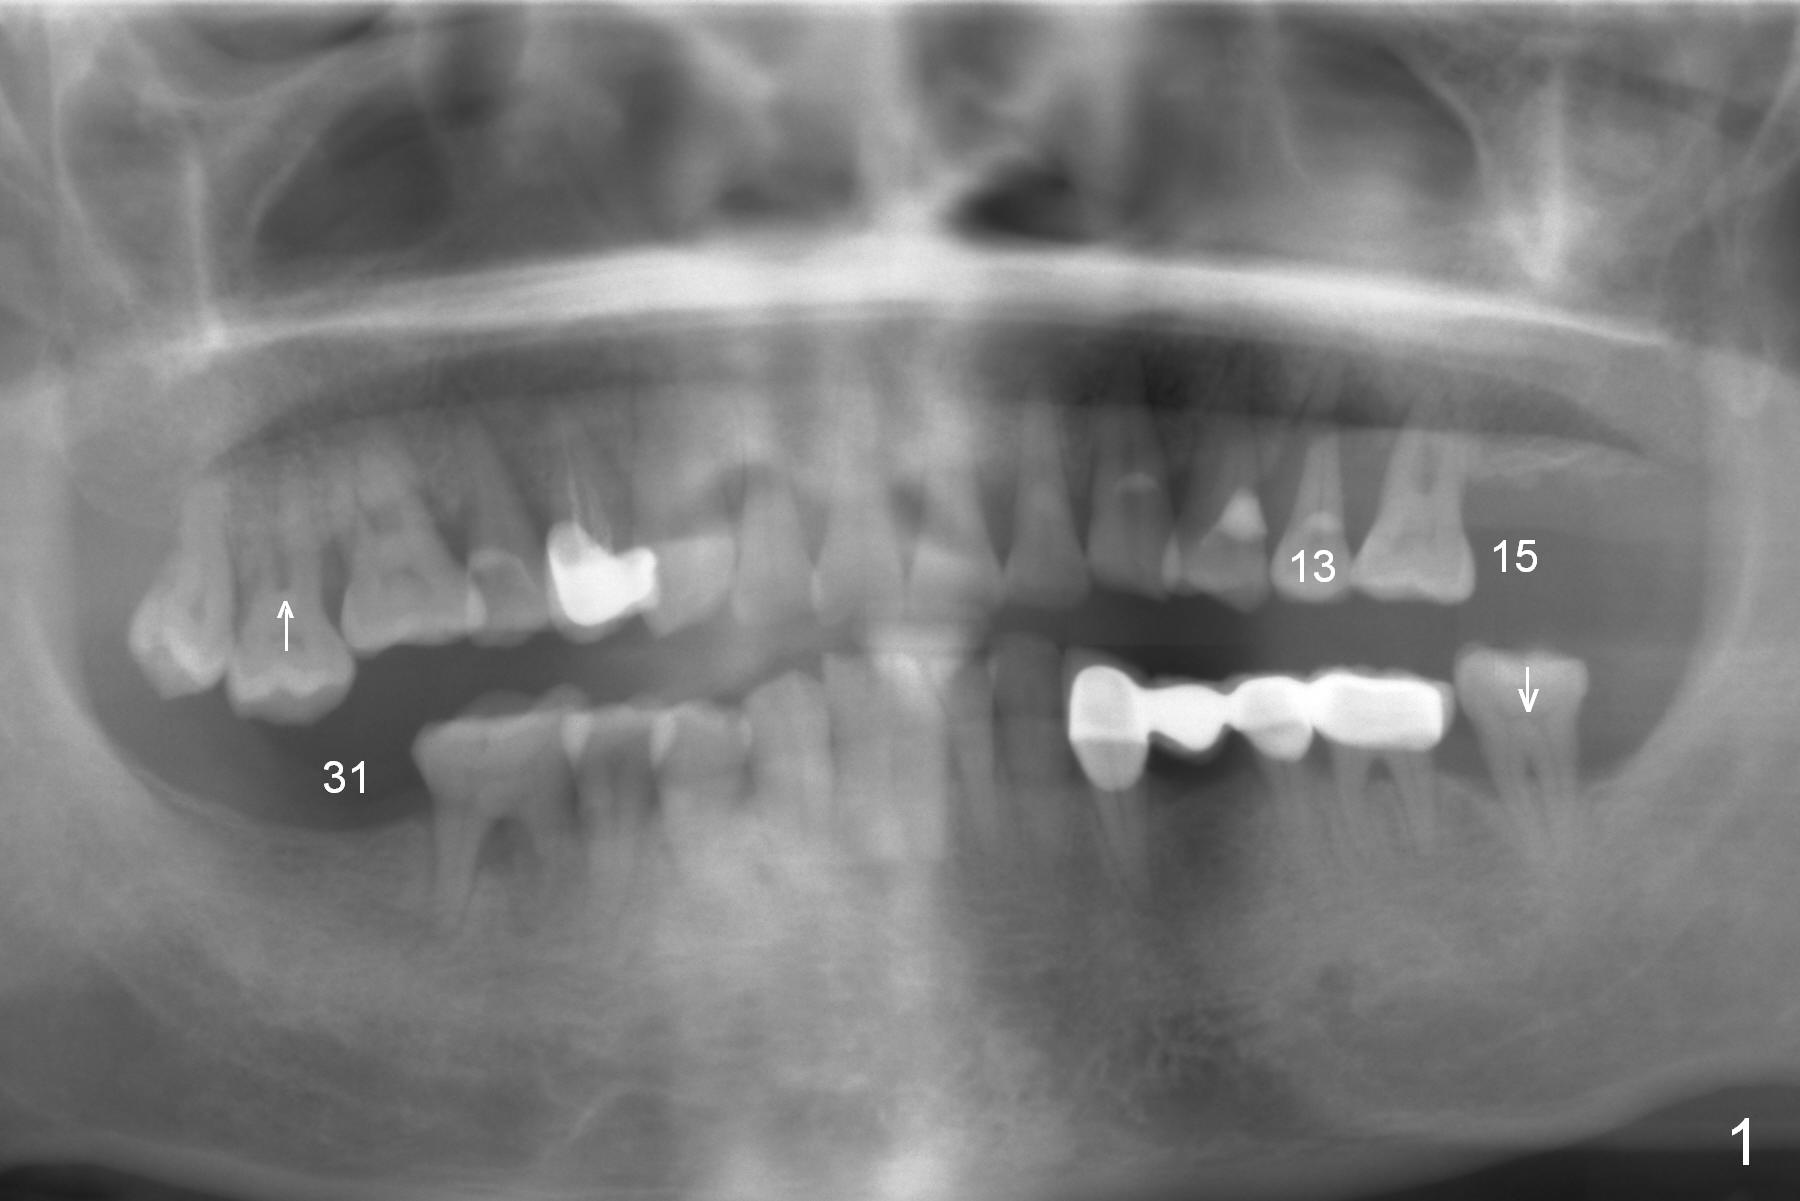

A 59-year-old man (smoker) is concerned about his oral conditions (periodontitis, partial edentulism (loss of #15 and #31) and #13 root fracture (*, possibly bruxism (sufficient clearance for provisional)), Fig.1,2) and wants to have a change. First SRP will be done on the left side with #13 extraction (Metronidazole, large socket (bone loss), large gauze) and immediate implant. Considering severe bone loss and bone height (sinus floor: red dashed line in Fig.2), a long narrow UF implant will be placed away from the lesion (most likely palatal if the buccal plate is lost) and deep with possible using 5-mm cuff abutment. To further prevent periimplantitis, smoke reduction is to be enforced preop (ask the patient about the cessation with care immediately prior to surgery) and PRF membranes (2-3) will be placed over the defective plate and into the sinus if needed. Also prepare sufficient amount of bone graft (especially to be placed mesial to #14).